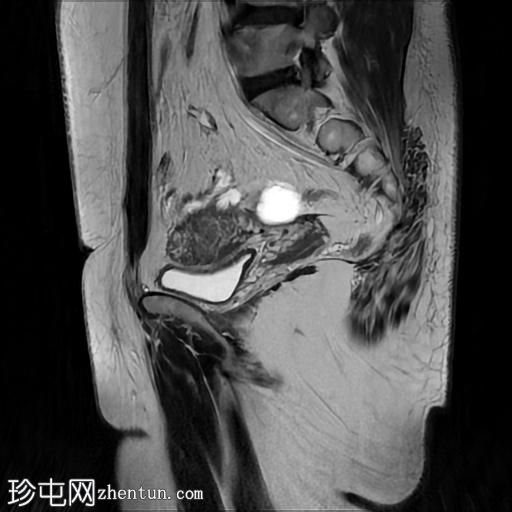

矢状位

T2加权像

右侧输卵管呈管状囊性扩张,直径达30 mm,提示输卵管积水,呈均匀液体信号,无实性成分。

左侧输卵管亦有轻度扩张,直径26 mm,符合输卵管积水表现。

右侧卵巢可见一单纯性卵巢囊肿,大小约35 x 40 mm,呈正常液体等效信号。

宫内节育器位置正常。

MRI 检查结果显示双侧输卵管积水和右侧卵巢单纯性囊肿。总体而言,所有附件和盆腔检查结果均显示良性 MRI 特征(O-RADS 2 类),无恶性肿瘤迹象。